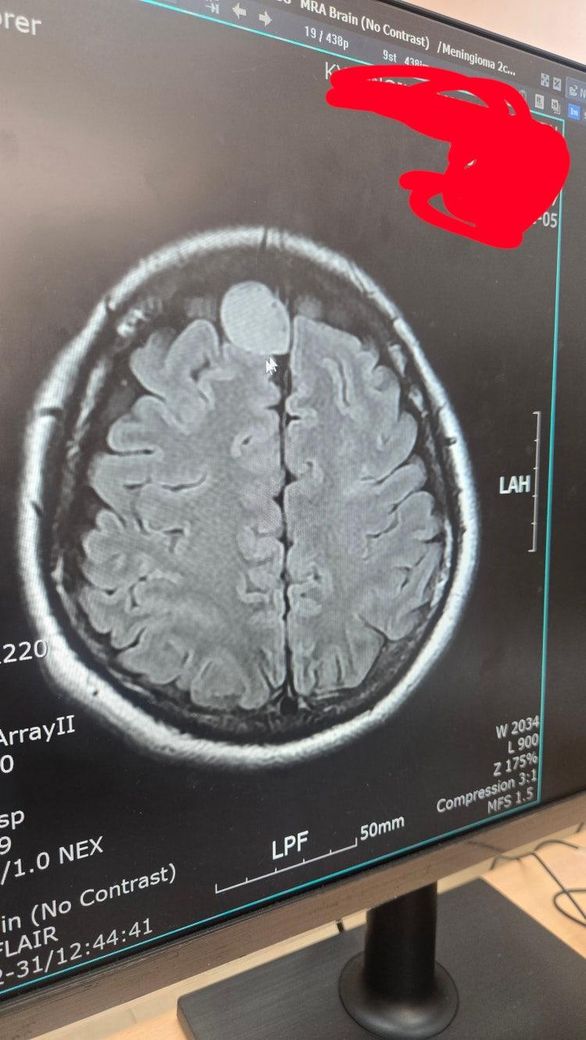

양성 뇌수막종이라고 진단받았습니다. 너무 괴롭고 힘든 나날들을 보내고 있어요.전두엽 우측 볼록면 2.2 센티 라고 해요. 근데 제 혹의 양상이 수막에서 생성된것이 맞나요? 모양이 꼭 아래 뇌쪽에서 생긴 혹같아서요.그리고 수술난이도도 궁금합니다.

• 제공해주신 영상은 축면 FLAIR MRI로 보이며, 병변은 우측 전두부 볼록면에 위치한 경계가 비교적 명확한 종괴로 관찰됩니다. 영상상 특징만 놓고 보면 뇌 실질 내부에서 발생한 종양이라기보다는, 경막(수막)에서 기원하여 뇌를 바깥쪽에서 압박하는 형태로 보이는 소견에 더 가깝습니다. 즉, “수막에서 생긴 혹”이라는 기존 진단과 영상은 서로 일치하는 방향입니다.

병태생리적으로 뇌수막종은 경막에서 발생하여 점차 자라면서 인접한 뇌를 눌러 변형시키는 양상을 보입니다. 이 경우 뇌와 종양 사이에 비교적 뚜렷한 경계가 형성되고, 종양이 둥글게 돌출되며 뇌를 밀어내는 모습이 특징입니다. 지금 영상에서도 종양이 뇌 안에서 퍼져 있는 형태가 아니라, 바깥에서 눌러 들어오는 형태를 보이기 때문에 전형적인 양성 뇌수막종의 영상 패턴과 크게 벗어나지 않습니다.

위치가 전두엽 볼록면이고 크기가 약 2.2cm라면, 일반적으로는 수술 접근성이 비교적 좋은 위치에 해당합니다. 중요한 혈관이나 뇌심부 구조와의 밀접한 침범이 없다면 수술 난이도는 상대적으로 “중등도 이하”로 평가되는 경우가 많습니다. 다만 실제 난이도는 다음 요소에 따라 달라집니다. 종양의 경막 및 두개골 침윤 여부, 정맥동과의 관계, 뇌부종 동반 여부, 환자 전신상태 등이 핵심 변수입니다.

결론적으로, 현재 영상만으로도 “수막 기원 종양”이라는 진단 방향은 타당해 보이며, 위치상 수술 접근성은 비교적 좋은 편으로 추정됩니다. 다만 정확한 수술 난이도와 위험도 평가는 조영증강 MRI, 정맥동 침범 여부 평가, 그리고 신경외과 전문의의 직접 판독이 반드시 필요합니다.